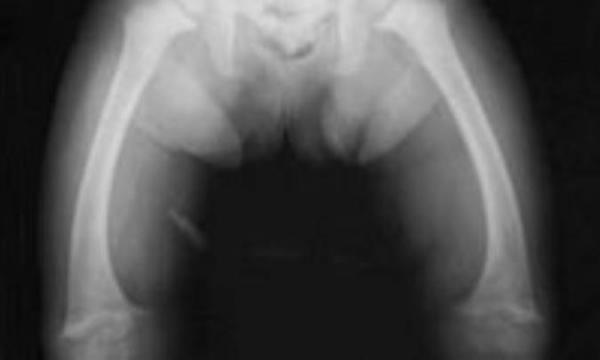

راشیتیسم یا نرمی استخوان یک بیماری استخوانی در بچه ها است که موجب ضعیف شدن استخوان، پاهای پرانتزی، و تغییر شکل در اندام ها میشود. در این بیماران به دلایلی کلسیم، فسفر یا ویتامین دی به اندازه کافی در اختیار فراوری استخوان قرار نمیگیرد.

مهمترین آنها عبارتند از خواب آلودگی، شلی و ضعف عضلانی، تاخیر در رشد، پای پرانتزی و مچ دست کلفت است. در موارد شدید ممکن است شکل قفسه سینه بچه تغییر کند. تشنج هم از دیگر علائم حالات شدید بیماری است. پزشک معالج بعد از معاینه بیمار، از رادیوگرافی استخوان ها و آزمایشات خون برای یاری به تشخیص استفاده میکند.درمان نرمی استخوان